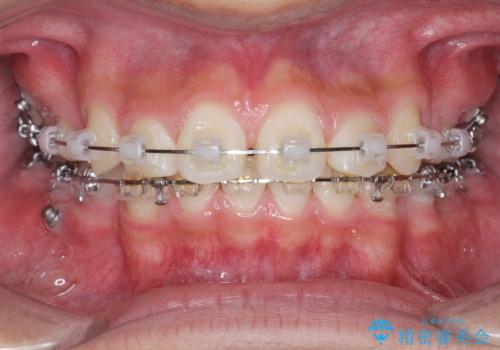

がちゃがちゃした前歯をきれいにしたい

- 前歯のがたつきが原因で歯ブラシしづらい、見た目を改善したい!と矯正治療を希望され来院されました。

スペースの不足が見られるため、小臼歯の4本抜歯を行いマルチブラケットを用いた矯正治療を計画します。

噛み締めが強く、治療に時間がかかりましたが矯正治療の仕上がりに満足いただくことができました。